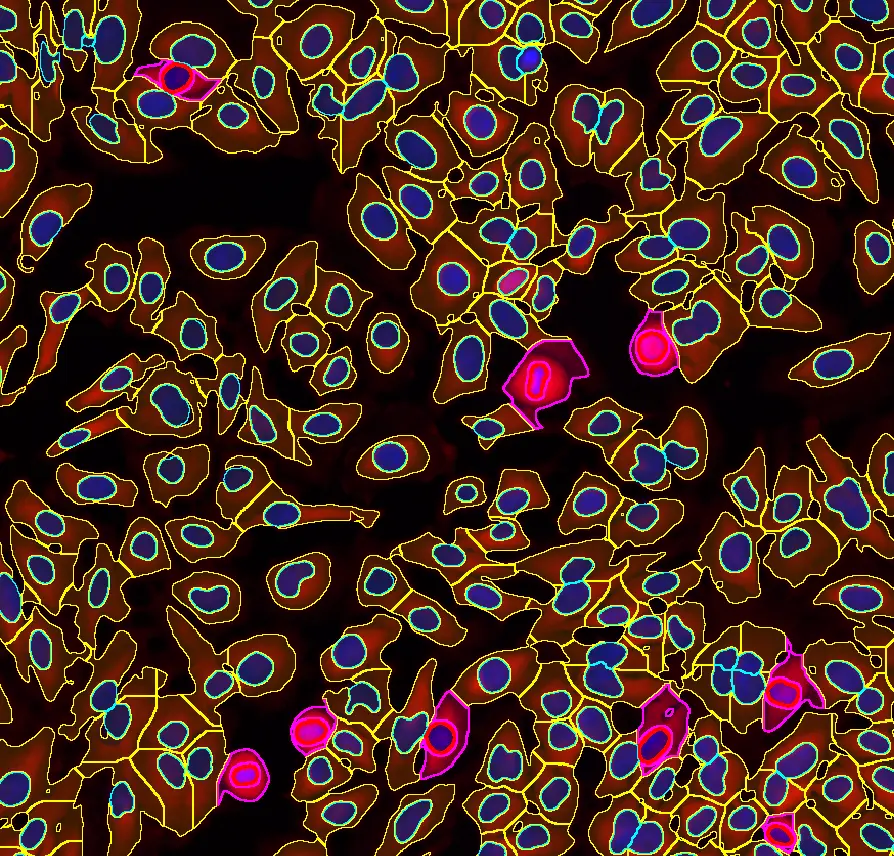

The IF Cardio Cell Culture Dot App provides cell segmentation, detection of cardiomyocytes (based an appropriate stain e.g. Troponin Red) and fibroblasts within cultured cardio cells plus one dot marker (CISH, FISH). The App outputs parameters such as number of cardiomyocytes, fibroblasts and dotpos cardiomyocytes, fibroblasts as well as number, area (μm²) and mean intensity of dots per cell.

Cardiomyocytes (red), fibroblasts (green)